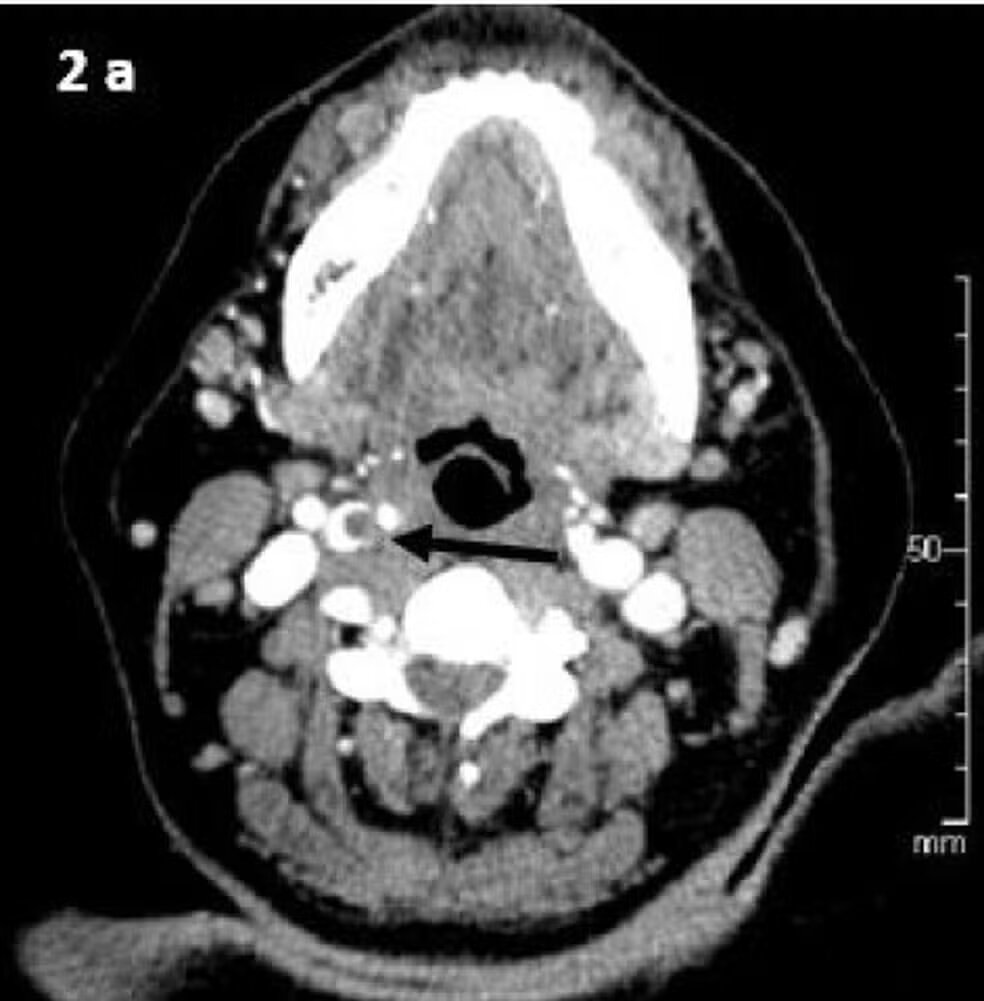

A reportagem conversou com especialistas, e o que eles explicam é que a pressão feita com a boca na região do pescoço causou uma lesão na artéria carótida, responsável por transportar sangue rico em oxigênio do coração para o cérebro.

O médico neurologista Felipe Aydar Sandoval, do Hospital Sírio-Libanês, explica que o nome técnico desse tipo de lesão é dissecção da artéria carótida, que é uma ruptura na parede da artéria, podendo causar sangramento e reduzir o fluxo sanguíneo para o cérebro.